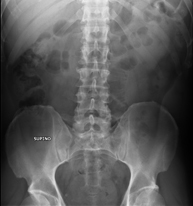

- RX Abdomen

Tècnica que usa els raigs X a través de la qual s'obtenen imatges de l'abdomen (estómac, intestí prim, intestí gros, fetge, ronyons, bufeta, pelvis òssia, etc.) per al seu estudi. - RX Columna lumbar

- Abdomen X-ray

An abdominal X-ray uses a small dose of radiation to obtain a two-dimensional image of the abdomen with its anatomical structures (stomach, small intestine, large intestine, liver, pancreas, kidneys, bladder, bony pelvis, etc.).